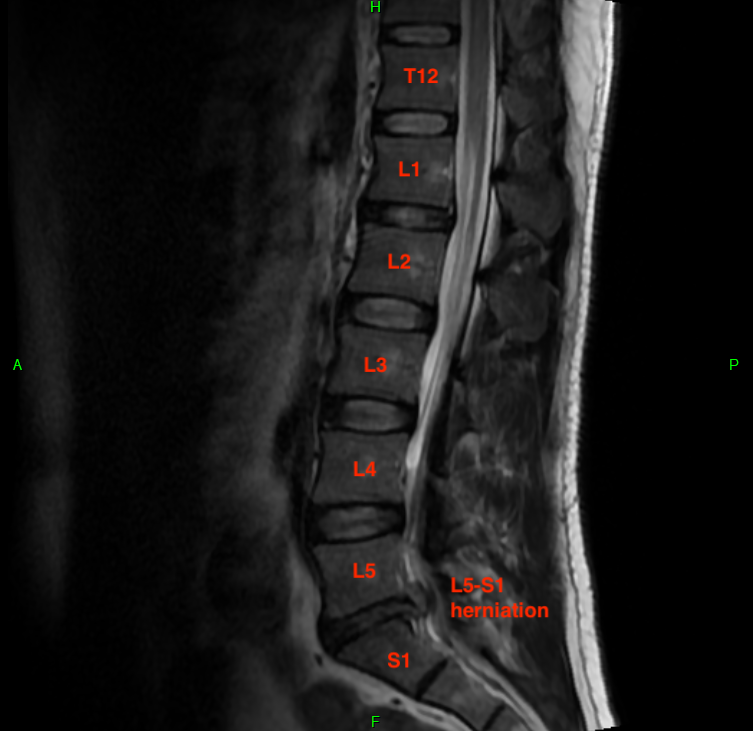

When taking MRIs, it's useful to correlate the sagittal (side) and axial (top) views. Imagine lying down and having a butcher slice you from right to left (sagittal) or from top to bottom (axial). The software that doctors use to examine MRIs is really cool in that you can scroll the mouse wheel on one diagram and it will show you your position on the correlated diagram. My MRI report listed a ton of deficiencies, most of which were minor issues that don't relate to my acute problem. This was the radiologist being diligent.

I want to show three levels for comparison. These are disc-level slices of my L3-L4 IVD, which is healthy. I've drawn cut lines on each image to show you how the slices correlate. These are T2-weighted images, which means water is hypersensitive (bright white). Tissue with high water content shows up as lighter, and you can see my relatively healthy IVDs all have a light center. That's because the nucleus pulposus is about 80% water and is responsible for about 80% of the axial load bearing of the spine. The remaining 20% of axial load is absorbed by the facet joints, which are a pair of hinge-like joints connecting adjacent vertebrae. They "fasten" the spine together and prevent excessive bending and twisting.

In the sagittal image, notice the bright white column just behind the vertebrae. This is the thecal (or dural) sac, which is the protective cavity for the spinal cord and cauda equina. In most adults, the spinal cord originates from the brain and terminates towards the end of the thoracic spine (T12) or around the beginning of the lumbar spine (L1). The spinal cord is quite thick and consumes much of the space inside the thecal sac. Mine ends at T12, so from there on down is the cauda equina, or "horse tail" of nerve endings. The thecal sac is still pretty wide despite only a handful of nerves passing through it, which makes it somewhat tolerant of encroachment from IVD herniations.

(Sagittal MRI)

This correlates on the axial view. The bright white triangle is the thecal sac and the black dots inside it are the cauda equina nerves. These nerves will exit from the thecal sac and pass through the neural foramen, a hole between two verbebrae. These holes are relatively small, but in a healthy person, there's plenty of space for the nerve roots to pass through without compressive forces.